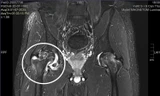

Dù qua được nguy kịch nhưng bệnh nhân đang đối mặt với di chứng mất thính lực

BS.Hoài Thu cho biết, sau 7 ngày được chăm sóc, điều trị tích cực, tình trạng bệnh nhân đã tỉnh táo, giảm đau đầu và đau vai gáy, không còn sốt. Tuy nhiên, biến chứng điếc tai vẫn chưa hồi phục, có thể để lại di chứng lâu dài.